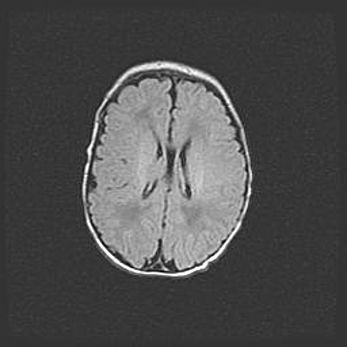

Открытая гидроцефалия.

Возраст: 6 месяцев 15 дней

Вес: 6200 г

Пол: женский

Окружность головы: 41 см

Срок гестации: 38 недель

Гидроцефалия головного мозга у новорожденных – это скопление избыточного количества цереброспинальной жидкости в головном мозге. Ее избыточное скопление в мозге приводит к патологическому расширению желудочков мозга (четырех полостей, расположенных в глубине белого вещества мозга, заполненных цереброспинальной жидкостью и связанных узкими проходами).

Открытый тип гидроцефалии (сообщающаяся) наблюдается тогда, когда нарушен механизм всасывания ликвора в системный кровоток. При этом типе причиной заболевания чаще всего является перенесенные ранее инфекции (например: менингит),  либо же наличие крови в субарахноидальном пространстве.